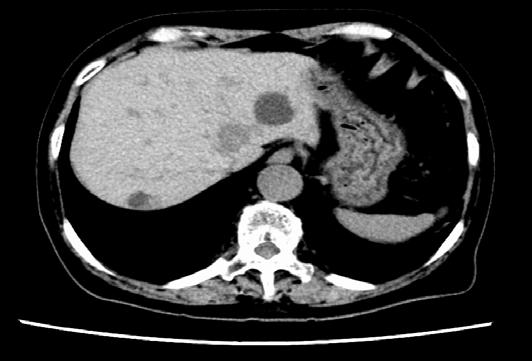

I hope these insights inspire curiosity, collaboration, and compassion, reminding us why we do this work. I hope to see you in Chicago, Illinois, for ASCO 2026.

Chair, ASCO 2025 Annual Meeting Scientific Program Committee; Director, Breast Cancer Research, Sarah Cannon Research Institute, Nashville, Tennessee, USA